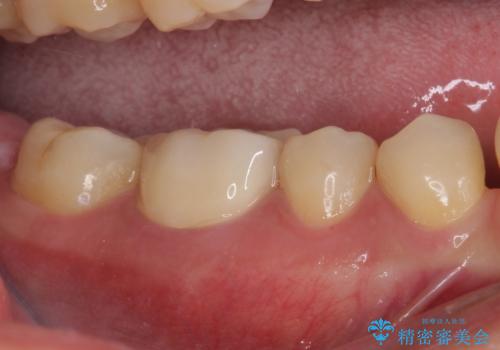

長年気にしていた銀歯を自然な色合いのセラミッククラウンに仕上げることができ、患者様には大変満足していただきました。